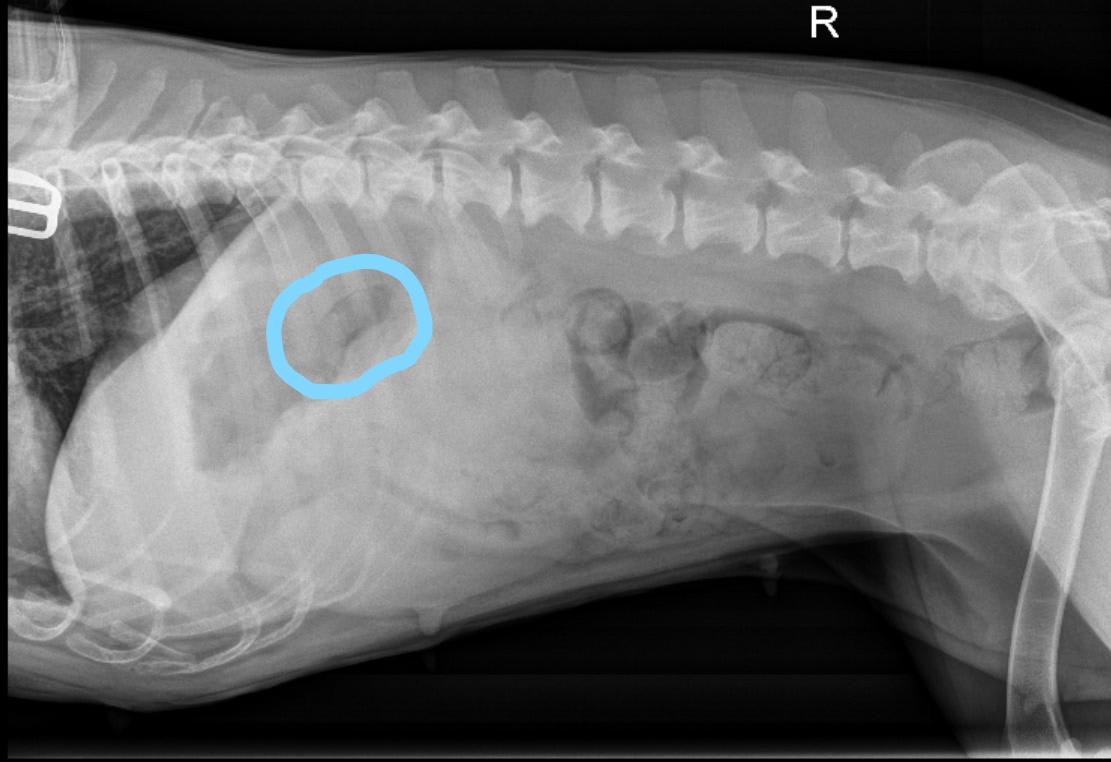

Hi, Ferg swallowed a piece of flat rubber ball about 1''x2.5'' a week ago. She has been asymptomatic. Xrays were taken and radiologist said there is no sign of foreign object. However, in the 1st pic, the outline seems to resemble the piece of rubber that was ingested. Is that the stomach? Am I overreacting? Also are there other anomalies shown on the Xray? Thank you for your time.

I see what you’ve circled in you picture but I think it looks more like a fold in the stomach, especially when you look at the other x-ray view. I would trust the radiologist - if Fergie starts to show symptoms of a gastric foreign body then you might want to have an ultrasound performed.